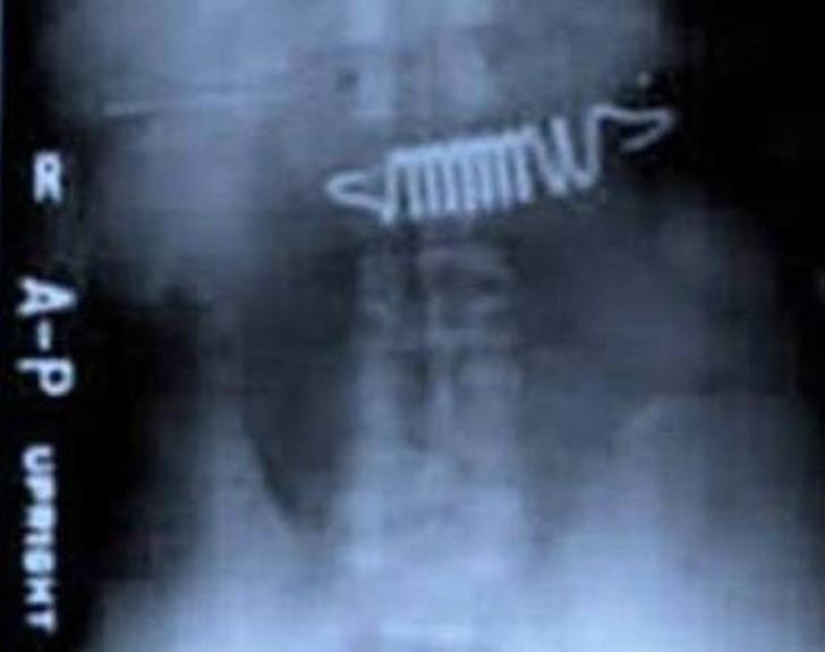

Muelles de cama.